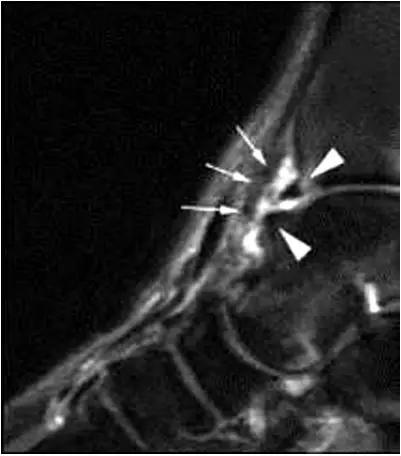

- MRI 检查示距后三角骨及周围软组织有水肿信号,距后三角骨和距骨之间正常的低信号纤维连接中断,出现液性信号。

3、MR表现:

- 三角籽骨或距骨后三角结构模糊和变形,T1WI信号降低, T2WI信号升高,

- 周围脂肪水肿,

- 踇趾长屈肌腱信号升高,见鞘膜积液,

- 胫骨后下跟骨上缘骨结构形态变化和信号异常,

- 三角籽骨和距骨退行性囊变。

三角籽骨综合征

三角籽骨综合征并跟腱滑囊积液